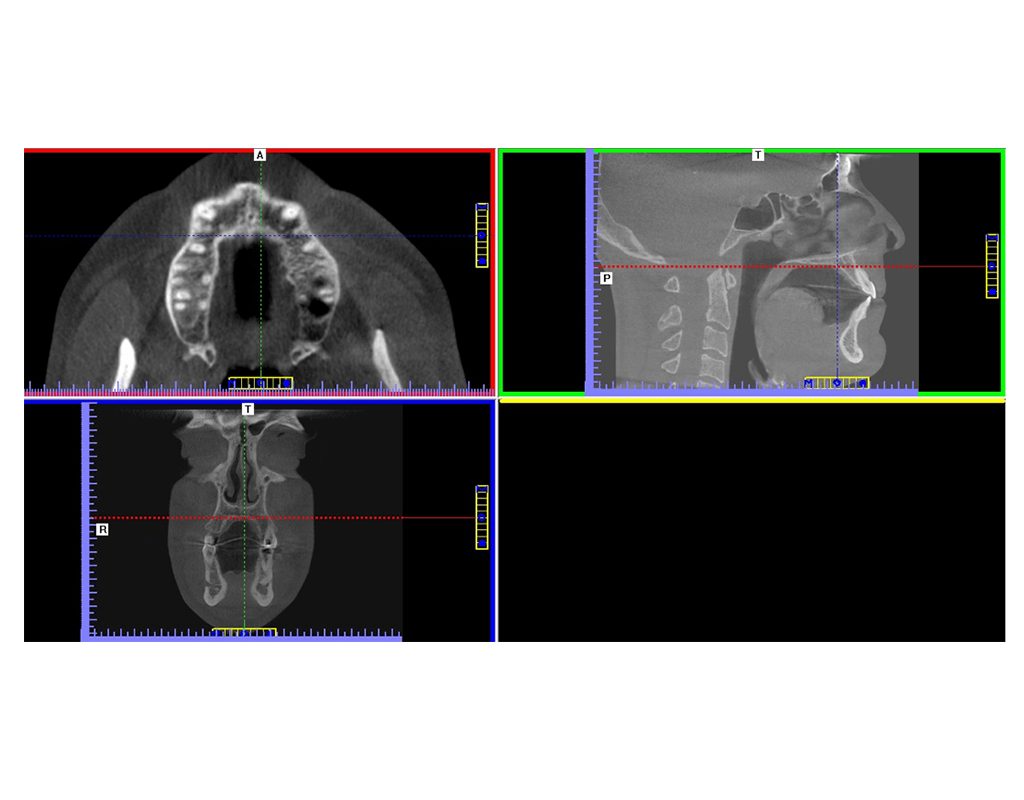

Tomografía de Haz Cónico (CBCT)

Es una técnica radiográfica que genera imágenes tridimensionales (3D), con mucho detalle de los dientes, tejidos blandos y huesos de la región maxilofacial, resultando en una menor radiación y una alta resolución.